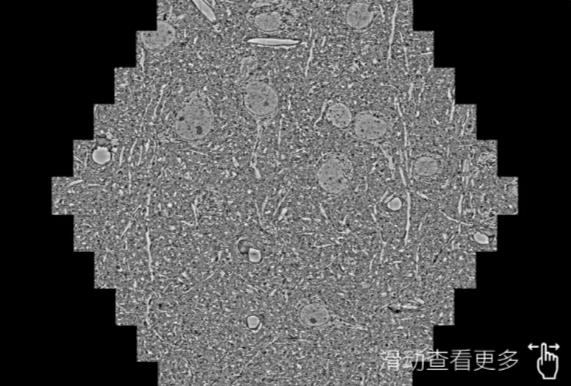

鼠脑切片。左图使用安康蔡司安康扫描电镜MultiSEM706对165μmx143pm面积区域成像,耗时仅需1.5秒。右图为鼠脑切片中30μm区域放大效果。样品由芝加哥大学B.Kasthuri提供。